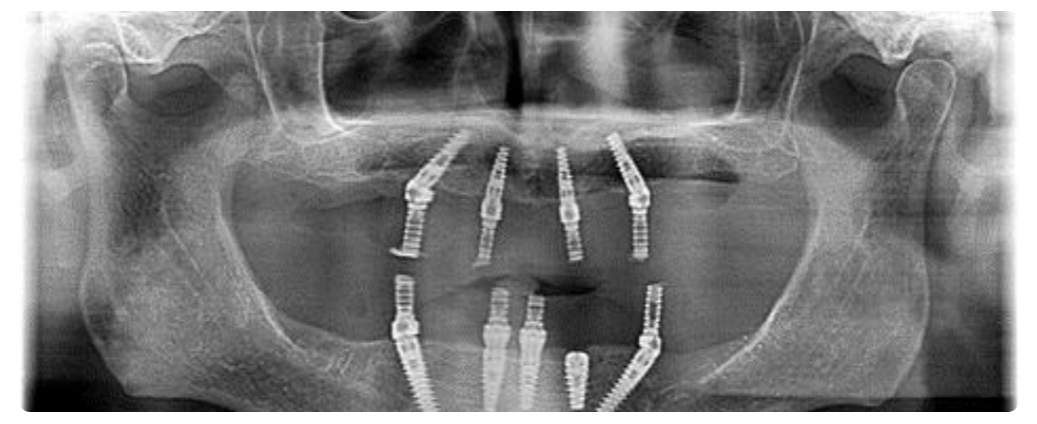

• This innovative approach involves the placement of four dental implants in a single jaw, where two implants are positioned vertically and the remaining two are angled.

Optimal Placement in Challenging Conditions

• This technique is particularly advantageous in cases where bone density is compromised, or where the sinus and nerve levels are in close proximity to the dental ridge. The strategic angling of implants allows for the avoidance of vital structures.

• The accompanying x-ray illustrates the placement of four implants in the upper jaw, showcasing the two straight and two angled implants.